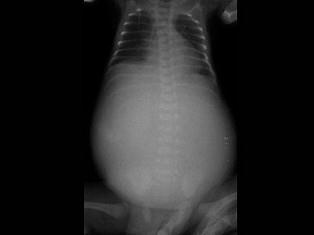

问题 女婴,7月。经常呕吐,腹部饱满、膨隆,消瘦。如图所示,最可能的诊断为?(?)

选项 A.消化道闭锁 B.十二指肠闭锁 C.消化道穿孔 D.肠套叠 E.肠扭转

答案 A